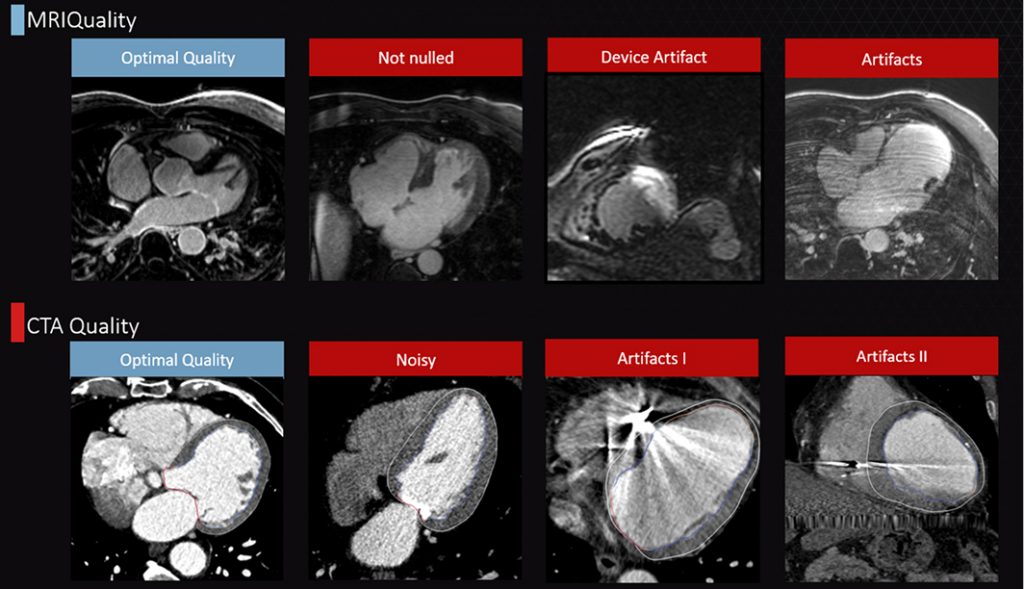

Assess the quality of your DICOM data.